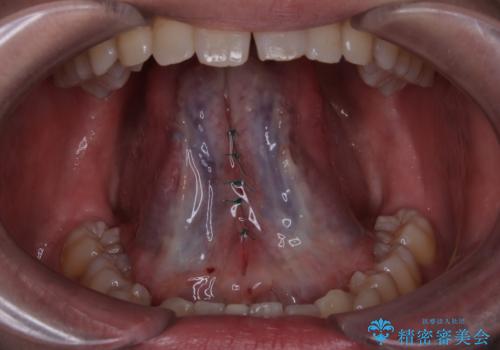

- 舌の動きが悪く、話しづらいとのことで改善を求めて来院されました。

舌の裏側にある小帯が短く、動かしにくい状態となっていました。小手術で形成することで滑舌の改善を計ります。

小帯の形成術によって舌の可動域が広がりました。

舌小帯形成術は、舌の下にある小帯(舌小帯)を調整する手術です。通常、舌小帯が短い場合に行われます。この手術は、滑舌の改善や発音の向上に使用されます。

手術は一般的に局所麻酔下で行われ、舌小帯を切開し縫合します。手術後は、通常数日から数週間で回復します。痛みや腫れがある場合は、医師の指示に従って適切な処置を行います。